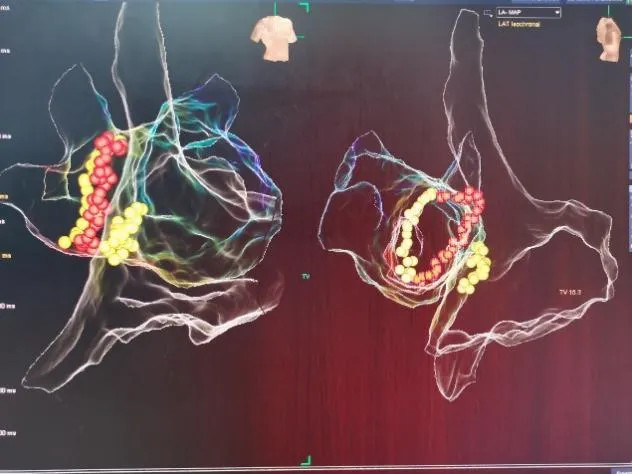

射頻消融術(shù)

三維電生理系統(tǒng)支持下的房性心動(dòng)過(guò)速射頻消融術(shù)

三維電生理系統(tǒng)支持下的心房顫動(dòng)+心房撲動(dòng)射頻消融術(shù)

房顫冷凍導(dǎo)管消融(陣發(fā)性房顫、高齡老人、心衰患者優(yōu)選)

長(zhǎng)程持續(xù)性房顫射頻消融術(shù)(環(huán)肺靜脈隔離+頂部線消融)